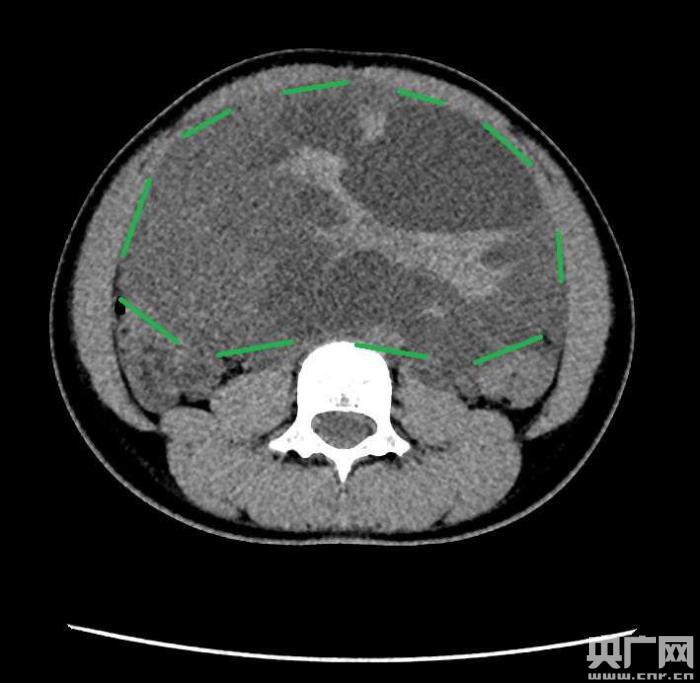

入院后,普外一科肖東主任向家長詢問了病史,仔細(xì)進(jìn)行了體格檢查,并完善腹部CT。CT結(jié)果提示,孩子的大部分腹腔、盆腔被一個(gè)巨大的腫瘤占據(jù),腸道、血管和腎盂都受到了不同程度的壓迫。從CT上看,腫瘤很可能起源于左側(cè)的卵巢。

手術(shù)中發(fā)現(xiàn),小琪腹中的腫瘤體積巨大,大小約為25×20×15厘米,表面光滑,來源于左側(cè)卵巢。醫(yī)生們首先將其與周圍的組織小心剝離,然后將這個(gè)占據(jù)孩子腹腔、盆腔大部分的巨大包塊完整切除,切除腫瘤后還重建了左側(cè)卵巢。剖開瘤體,發(fā)現(xiàn)瘤體為囊性及實(shí)性混合組成,瘤體內(nèi)部充盈著粘液狀的液體,重量達(dá)到了3000克。術(shù)后小琪病情穩(wěn)定,測(cè)量腹圍從術(shù)前的72厘米減小到了62厘米。